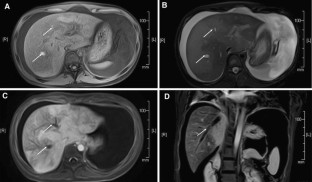

We retrospectively compared MRI results of 24 patients with acute and 82 patients with chronic BCS using Mann–Whitney U test for ascites volume, and Fisher’s exact test for intrahepatic venous collaterals and extra-hepatic venous collaterals. In the acute group, MRI findings suggested thrombosis in hepatic vein (HV) in all acute patients and additional inferior vena cava (IVC) thrombosis in 5 patients. In the chronic BCS group, 6 and 15 patients showed solitary obstruction either in the IVC or HV, respectively, while 61 patients showed combined IVC and HV obstruction. More patients with acute BCS presented with ascites accompanied with high signals on T2WI from intravenous obstructive lesions. Further, the average maximal spleen diameter in patients with acute BCS, and the ratio of patients with acute BCS developing intrahepatic venous collaterals and extra-hepatic venous collaterals were also lower compared with chronic BCS. All these differences were statistically significant.

Fig. 2